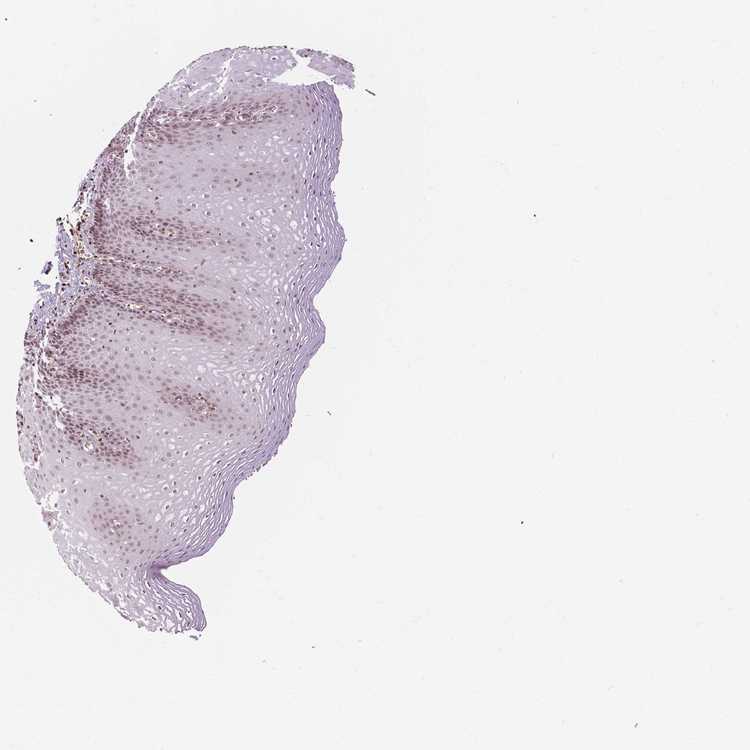

TISSUE PRIMARY DATA ESOPHAGUS Show tissue menu

Esophagus

ESOPHAGUS - Antibody stainingi

Antibody staining in the annotated cell types in the current human tissue is reported as not detected, low, medium, or high, based on conventional immunohistochemistry profiling in selected tissues. This score is based on the combination of the staining intensity and fraction of stained cells.

Each image is clickable and will lead to virtual microscopy that enables deeper exploration of all samples and also displays staining intensity scores, fraction scores and subcellular localization as well as patient and tissue information for each sample.

Antibody HPA042128Antibody HPA049883Antibody HPA051156Antibody CAB004298

Squamous epithelial cells Not detectedLowMediumMedium